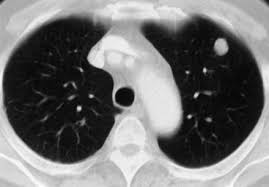

-Chest X Ray typically shows bilateral alveolar infiltrates, and CT scan will show widespread patchy airspace opacities that are more apparent in dependent lung zones.  This will likely progress to a ground glass appearance